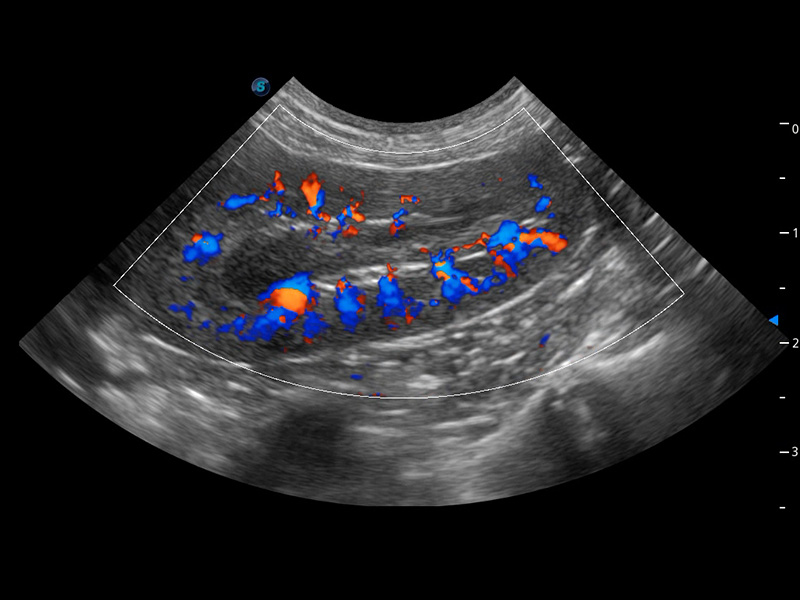

ProPet 60 作為一款高端臺(tái)式動(dòng)物超聲設(shè)備,為動(dòng)物醫(yī)生的日常診斷提供了一系列貼合動(dòng)物臨床需求、解決臨床實(shí)際問(wèn)題的高級(jí)成像功能。憑借全系列高清探頭,滿(mǎn)足醫(yī)生對(duì)腹部、心臟、生殖、淺表、肌骨等成像的所有需求,切實(shí)幫助您提升檢查效率,提高診斷信心。